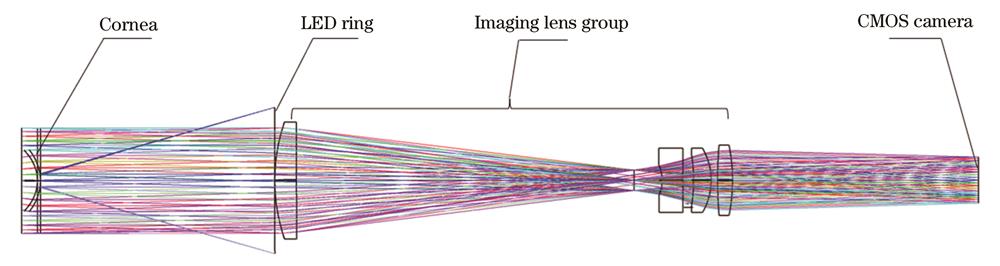

A human eye autofocus and pupil center auto-alignment system for ophthalmic measuring instruments is built. The system is mainly composed of a fixed vision module, an LED lamp bead plate, an imaging module, a three-axis electric displacement stage, and a head holder. By analyzing the characteristics of human eye images, an autofocus algorithm based on a four-neighborhood-multi-directional and two-level gradient function (FMTG algorithm) was proposed. The algorithm replaces the center pixel with the mean value of the center pixel and the four-neighborhood pixel for calculation, calculates the two-level gradient in the horizontal direction, vertical direction, and direction with an oblique of 45° at the same time, and takes the product of the two-level gradient operators as the sharpness evaluation value. A pupil center positioning algorithm (LPC algorithm) based on the intelligent region of interest (ROI) window of a convolutional neural network was proposed. The algorithm extracts the image coordinates of the pupil center and optical axis for alignment through steps including the extraction of the pupil region of interest, histogram-based binarization segmentation, and high-precision ellipse recognition and fitting. The performance of the proposed FMTG algorithm was verified by the system built in this paper and by actually shooting four groups of human eye-defocused image sequences. Six commonly used evaluation functions were selected for comparison, and their normalized sharpness evaluation curves were drawn. Three quantitative indicators, namely, single-frame processing time, sharpness ratio, and sensitivity, as well as two important properties such as unimodality and accuracy, were selected to comprehensively evaluate the performance of the functions. The performance of the proposed LPC algorithm and other algorithms for comparison was evaluated in terms of the average computation time, accuracy, and average error through the test set of real-shot human eye images. In addition, the proposed LPC algorithm was tested under complex conditions with different illumination and partial pupil occlusion to evaluate the universality of the algorithm.

2 系统组成

应用于眼科测量仪器的人眼自动对焦及瞳孔中心自动对准系统如

图 1. 人眼自动对焦及瞳孔中心自动对准装置组成结构

Fig. 1. Structure of human eye auto-focus and pupil center auto-alignment device